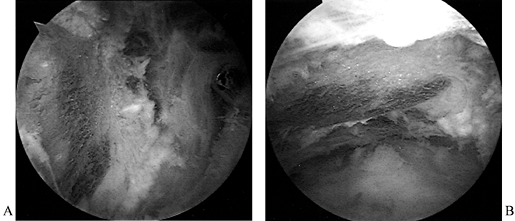

-

and reparability of a tear (Fig. 79.11 and Fig. 79.12). If the tear appears reparable with or without mobilization of the cuff, proceed with arthroscopic repair. (See below for the management of irreparable tears.) After decompression, perform arthroscopic mobilization of the cuff if desired, or proceed with open surgery.

Figure 79.11.

Arthroscopic view of a full-thickness tear with an obvious acromial

spur overhead and an intact biceps tendon beneath a slightly retracted

tear of supraspinatus.